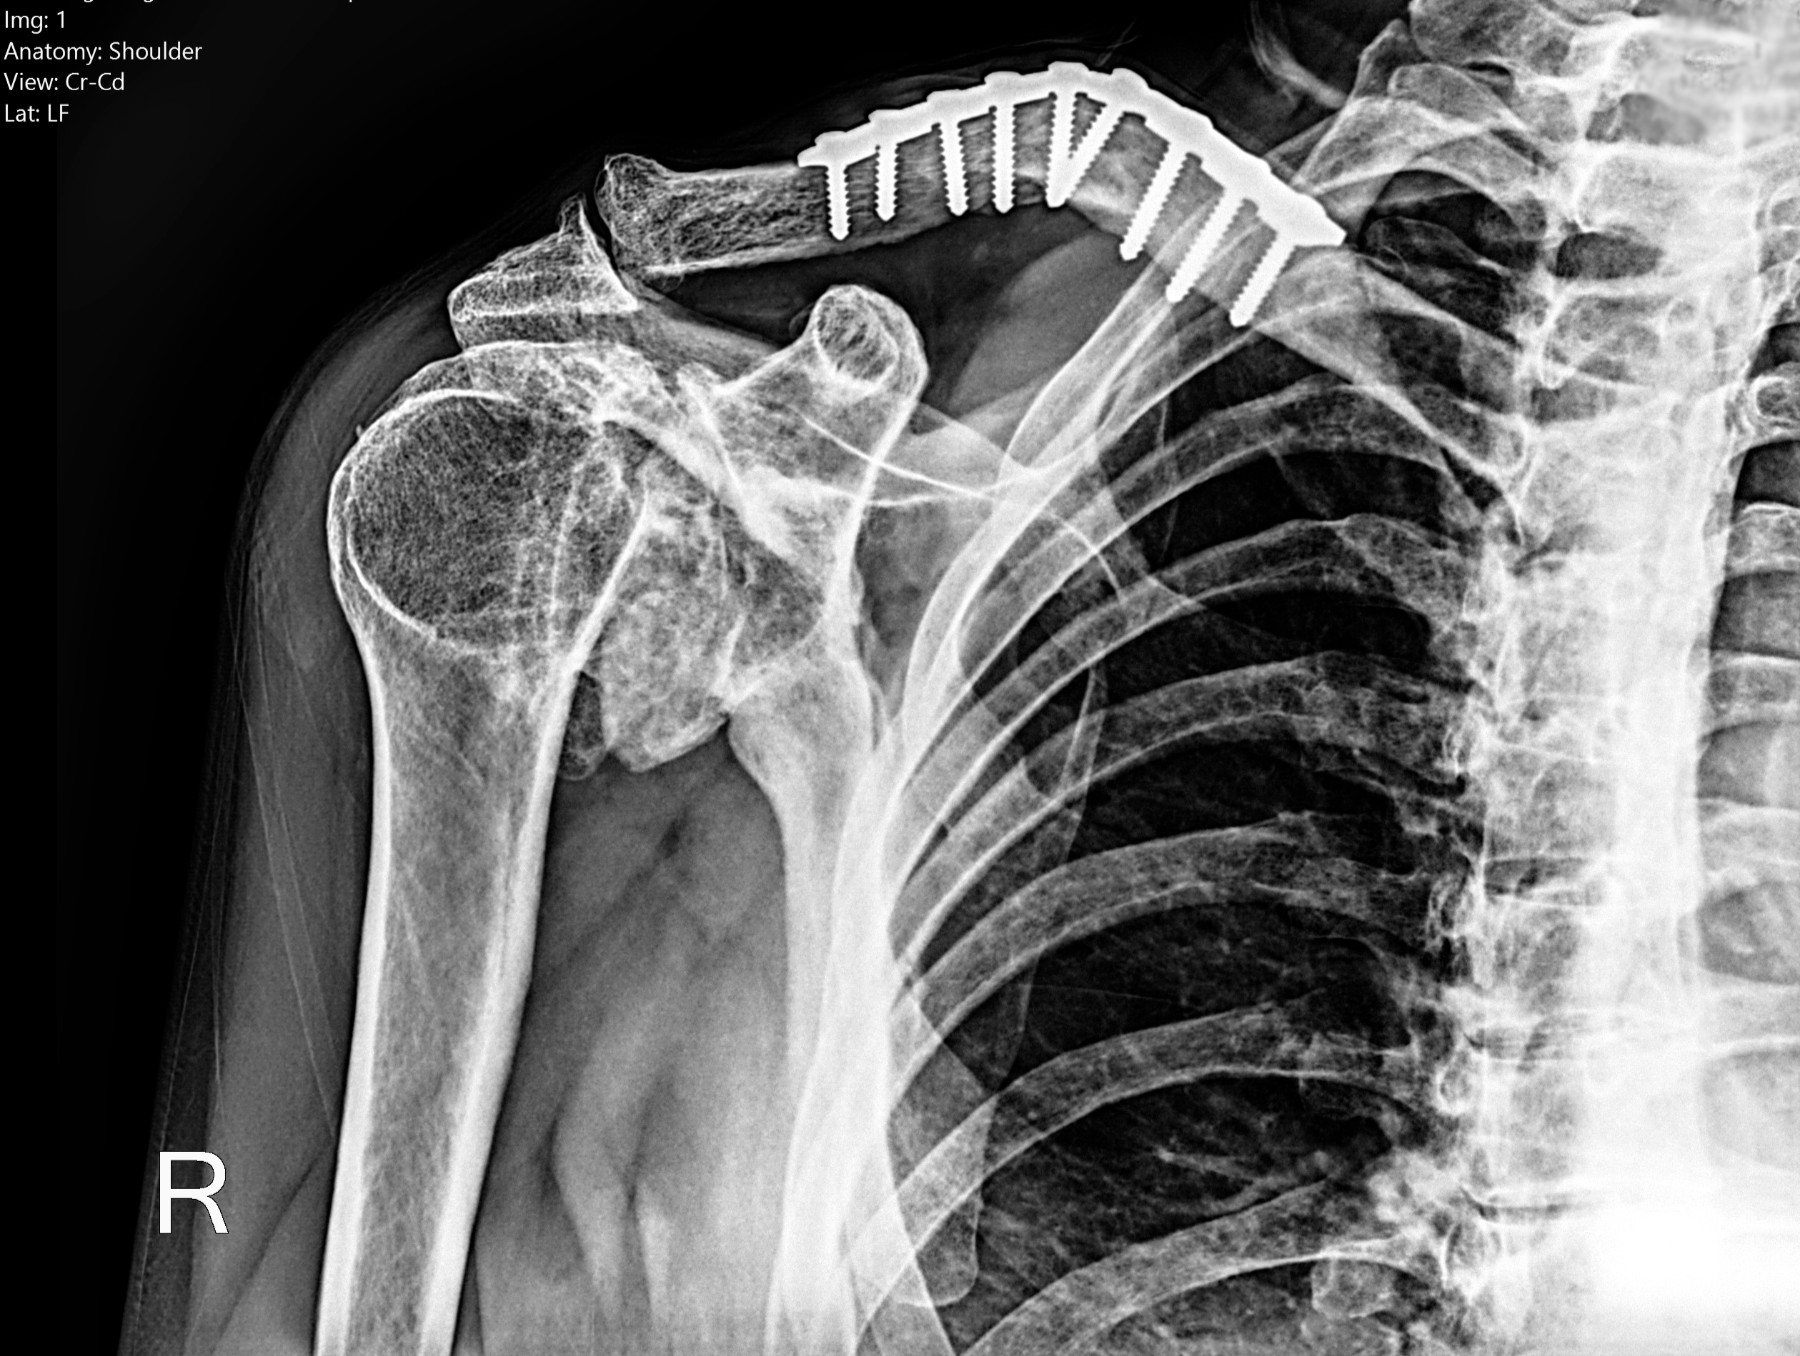

Radiología Digital como Herramienta Complementaria en el Dictamen de Bienes Muebles

Desde el descubrimiento de los rayos “X” y las placas radiográficas por Wilhelm Conrad Roentgen y su posterior difusión a través de la Asociación Físico médica de Wurzburg el 28 de diciembre de 1895, que fue la primera asociación que habló de los nuevos rayos que podían penetrar el cuerpo y fotografiar los huesos, ha habido muchos cambios tanto en la forma de obtener, procesar e incluso en la forma de visualizar, manejar y almacenar las placas radiográficas.